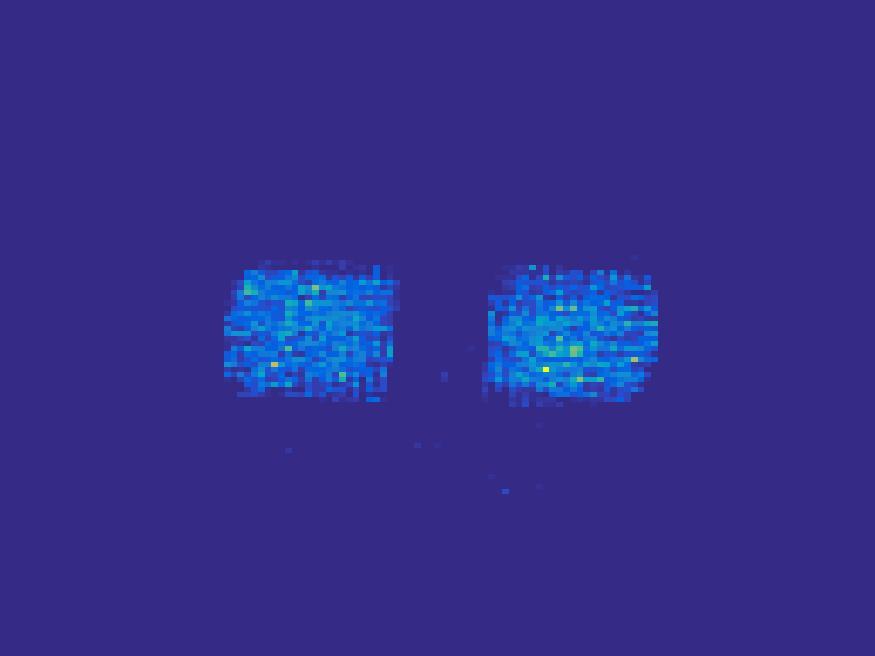

In order to test the performance of the proposed method in a more realistic scenario, we perform a Monte Carlo simulation for dynamic SPECT imaging. First, we created a phantom image consisting of three circles as region of interests, shown in Figure 13. The TAC over a time period of 90 time steps of the outer and the two inner circles were displayed in 13(b).

For each single frame, the photon counts is a probability proportional to the concentration in every region. The events are detected by a virtual double heads gamma camera rotating around the patient by degrees per time step, which consists of detector bins. Every simulated decay event is projected and counted by the corresponding detector bin.

We set the number of events counted by the detector as and ) times the average concentration in one pixel of two different tests. The signogram images the count in each bin of two settings are shown in Figure 14.

Based on the sinogram data, we compare the proposed method with the alternating EM algorithm. The results for both test cases are shown in Figure 15. We can see that for the case of a low count number, the proposed method is able to reconstruct the regions properly. Within a number of iterations, the algorithm presents a reasonable reconstruction of the region of interest and the corresponding regional tracer concentration curves.